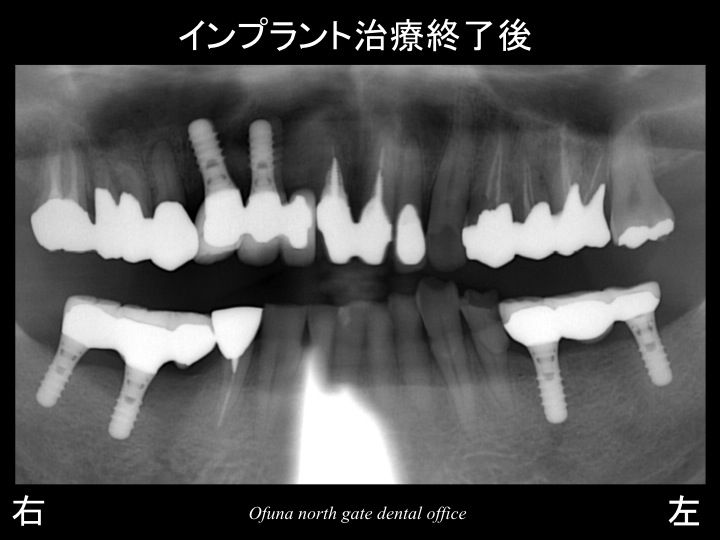

以下は、インプラント治療が終了した状態です。

使用したインプラントは、

アンキロス インプラント と

ストローマンインプラント(ITIインプラント)

です。